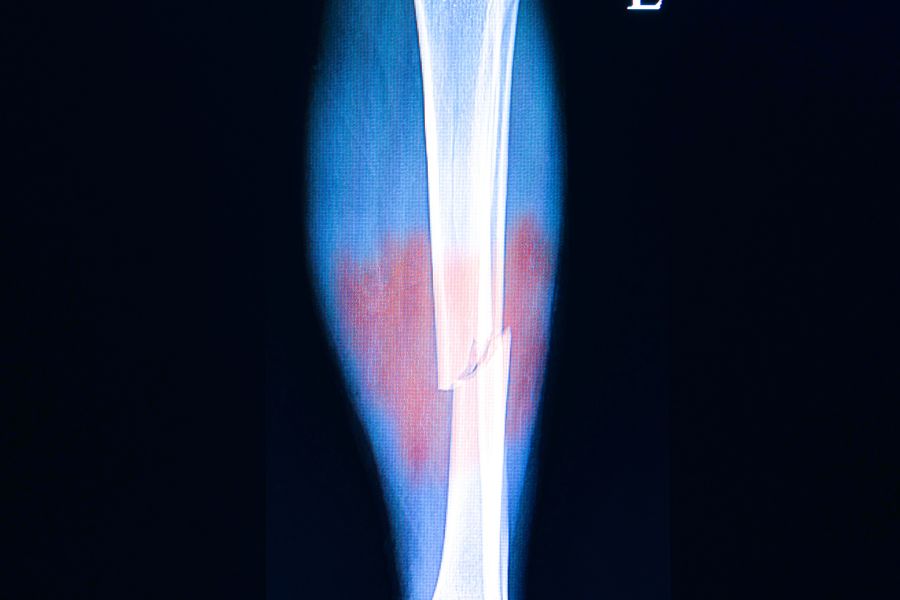

Stres kırığı, kemik üzerine uygulanan tekrarlayıcı yüklenmeler sonucu oluşan, tam kırık olmayan ama mikroskobik çatlaklardan oluşan bir kemik hasarıdır. Zamanla bu çatlaklar büyüyerek tam kırığa dönüşebilir.

• Röntgende başlangıçta görünmeyebilir, MR ile daha net saptanır